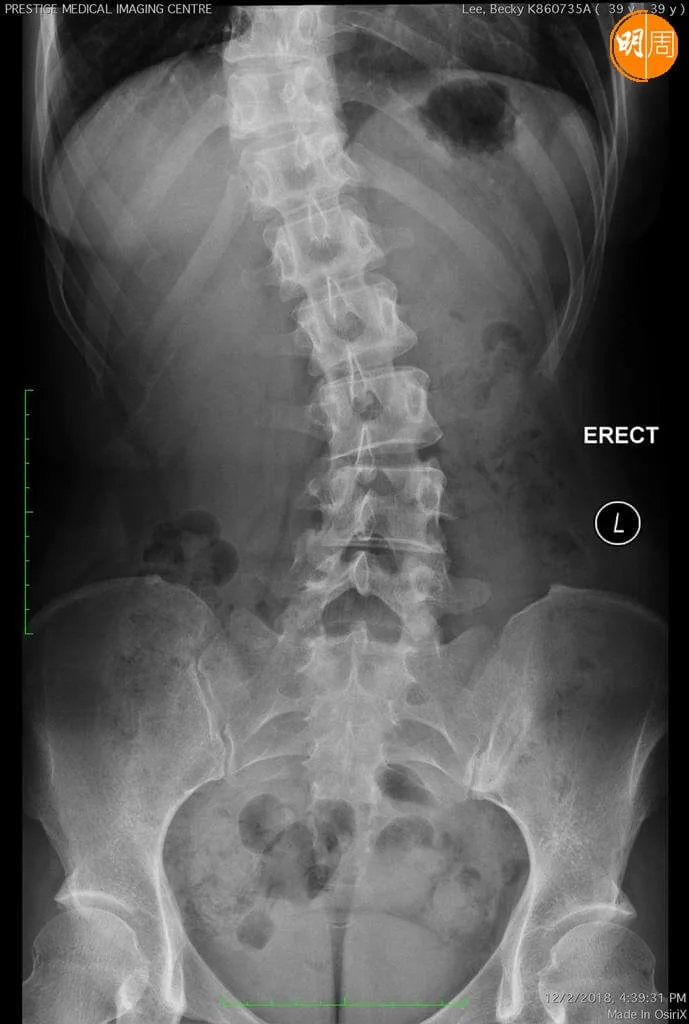

脊柱側彎,指背脊骨向左或右彎曲,呈現「C」或「S」形,是常見的都市病,由於彎曲位置不同,影響範圍也有別,身體肌肉在不平衡的情況下,脊柱附近神經線長期受壓,出現腰背痛等徵狀,註冊物理治療師周偉明,教大家強化核心肌肉,增強脊柱的柔軟度和活動幅度,減低側彎惡化情況。